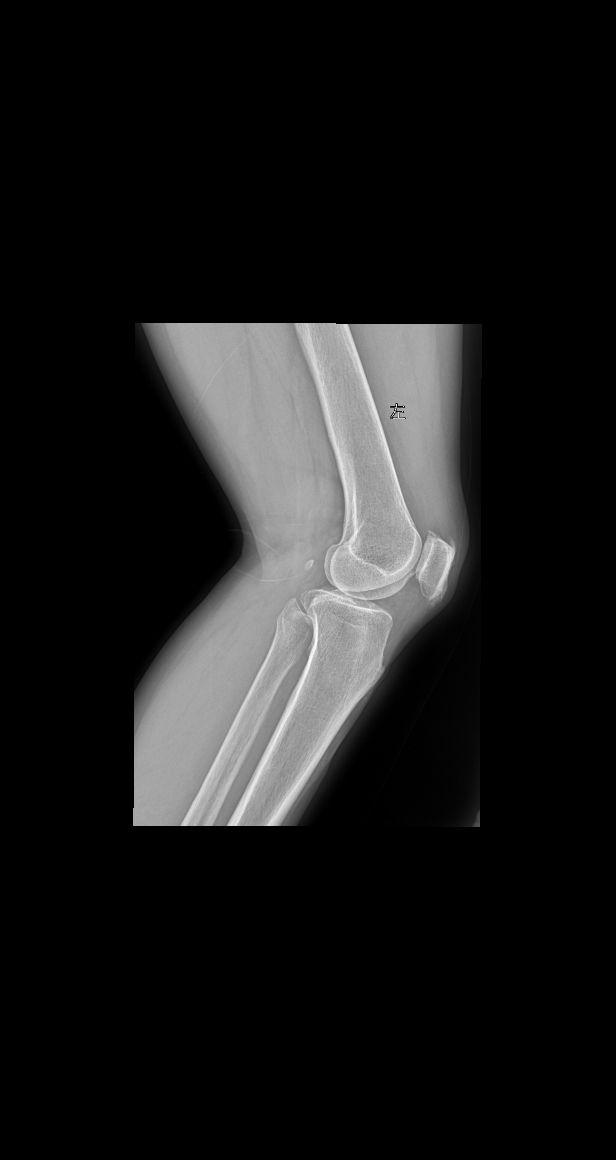

老师们拍摄膝关节采取站立位还是卧位